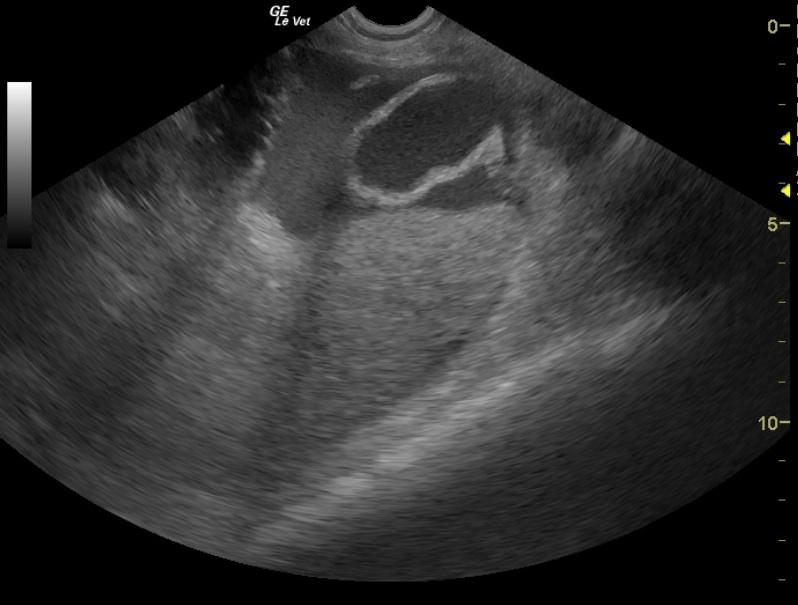

An 11-year-old FS DSH with history of asthma was presented for acute hind leg paresis. Abnormalities on physical examination were tachycardic, pronounced gallop rhythm, absent femoral pulses, all four extremities were cool, and she was unable to stand. The patient was treated with Lasix, nitroglycerin, and heparin. Within a few hours she was able to ambulate on her own but was knuckling over on all fours